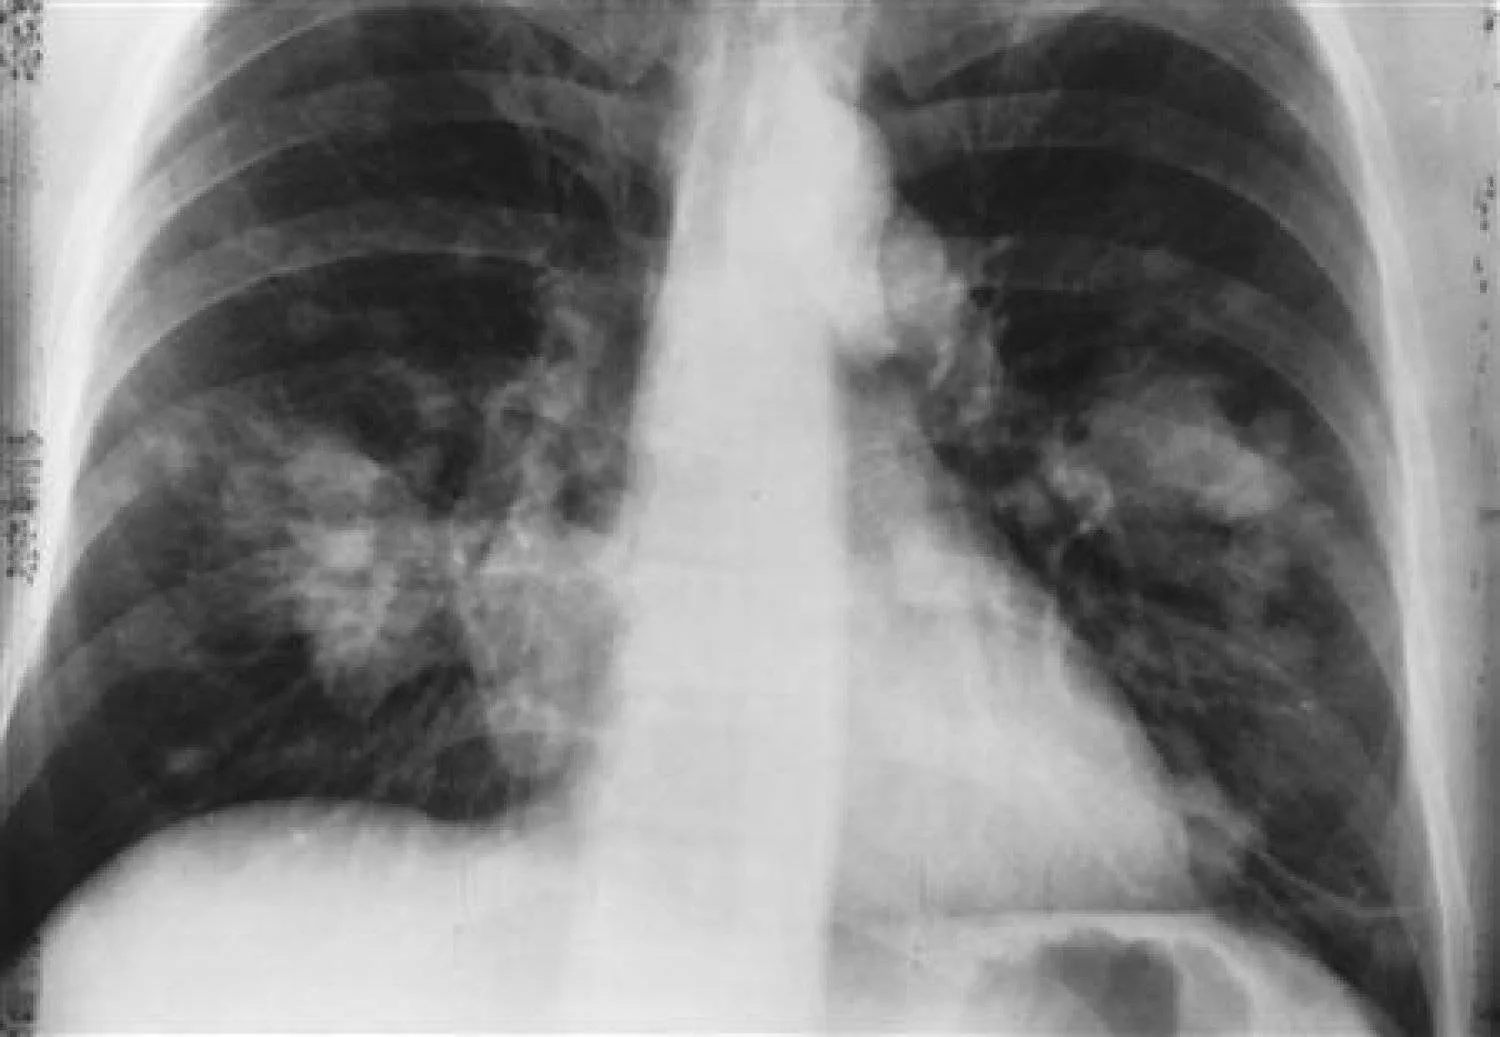

وقالت الوكالة إن سرطان الرئة لدى غير المدخنين يحدث أيضاً على شكل سرطان غدي، وهو النوع الذي أصبح الأكثر انتشاراً بين الأنواع الفرعية الأربعة الرئيسية للمرض (السرطان الغدي، وسرطان الخلايا الحرشفية، وسرطان الخلايا الصغيرة، وسرطان الخلايا الكبيرة) لدى كل من الرجال والنساء على مستوى العالم.

وشكل السرطان الغدي 45.6 في المائة من حالات سرطان الرئة العالمية بين الرجال و59.7 في المائة من حالات سرطان الرئة العالمية بين النساء في عام 2022. وكانت الأرقام على التوالي 39.0 في المائة و57.1 في المائة في عام 2020.